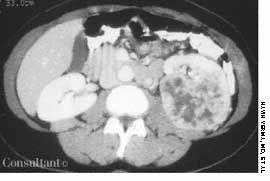

A chest film disclosed multiple nodules in both lungs. A biopsy of the nodules confirmed metastatic renal cell carcinoma. There was no evidence of endobronchial lesions on bronchoscopy.

Drs Mahesh Duggal, Krishna Badhey, and Arunabh of Queens, NY, explain that the roentgenographic pattern of multiple metastatic lung nodules varies from diffuse micronodular shadows to large, well-defined masses, or “cannonballs.”

The cannonball lesions caused the patient's persistent cough and hemoptysis. Extensive bone metastases were discovered as well; the patient was referred for radiation therapy.